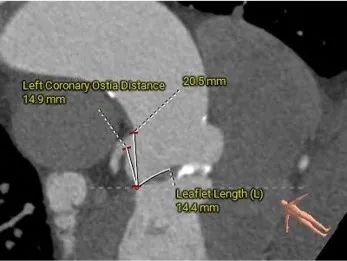

左冠15.7,右冠19.4,综合分析冠脉阻挡风险适中

瓣上多平面分析

• 左、右冠高度可,切线位测量,无冗长瓣叶,结合瓦氏窦、STJ 内径综合预估,冠脉阻塞风险适中